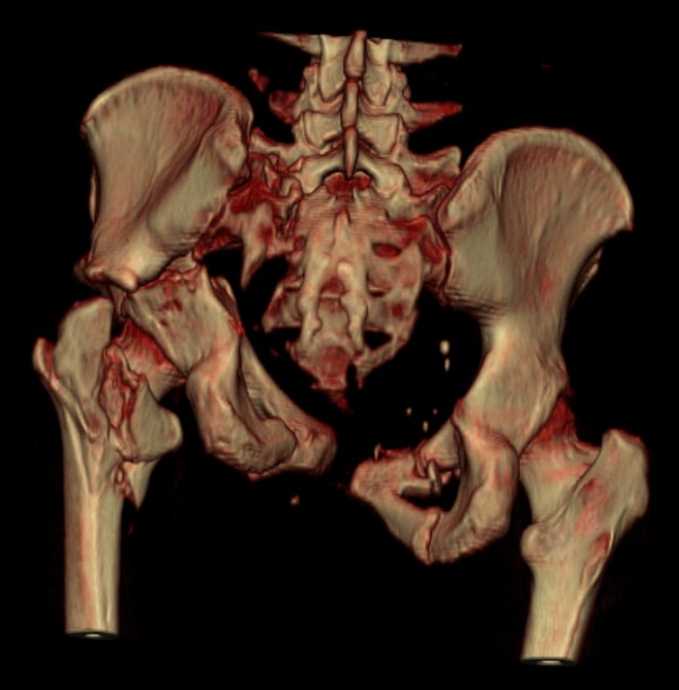

Больная 43 года (промышленный альпинист), 28.07.08 в результате падения с 5 этажа получила политравму: Перелом свода и основания черепа. Вертикально-нестабильное повреждение таза, осложнённое разрывом мочевого пузыря. Чрезвертельный перелом левого бедра. Перелом правой таранной кости, переломовывих правой кубовидной кости. Тупая травма живота, разрыв печени, ушиб почек. Забрюшинная гематома. В день травмы - лапаротомия, ушивание ран печени. Разрыв мочевого пузыря не диагностирован. Течение болезни осложнилось развитием мочевого затёка и обширной пред- и забрюшинной флегмоны, сформировался свищ мочевого пузыря. 19.8.2008 вскрытие, дренировние флегмоны, ревизия мочевого пузыря, обтурация мочевого свища (свищ закрылся в октябре), 1.10.2008 некрэктомия, пластика по Шеде-Лидскому правой кубовидной кости. По результатам КТ диагностирован рак правой почки (диагностическая находка), 8.10.2008 нефрэктомия справа. Переломы велись консервативно. Имеется вертикальное смещение левой половины таза с выраженным отведением крыла (клинически подвижности нет), несросшийся низкий двухколонный перелом левой вертлужной впадины с потерей конгруэнтности, укорочение около5 см, застарелый разрыв лонного сочленения, неправильно сросшиеся переломы обеих ветвей правой лонной кости с укорочением, патологическая подвижность лоно-седалищного фрагмента слева. Правая нижняя конечность неопорна, несмотря на то, что лежа прямую ногу поднимает, ходит на левой ноге (ортопедическая обувь) с костылями, справа тазобедренный ортез. Седалищные нервы работают.Урологи отпустили больную на 6 мес.